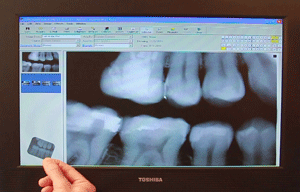

Digital Radiographs (Single and 3D)

Digital Radiography uses 40% to 60% less radiation than traditional film and does not require any chemical processing which reduces our impact on the environment. Digital images can be enlarged to show more detail and help in early detection of disease.